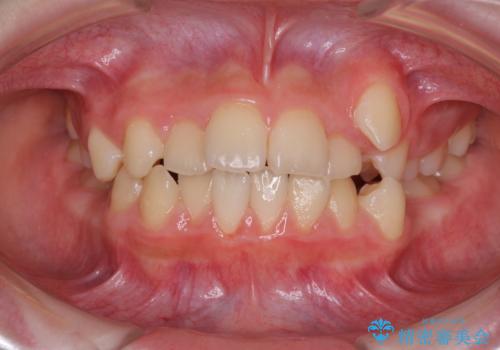

- 八重歯と乳歯が残っていることを気にして来院された患者様です。

乳歯が3歯残っており、下顎は左右ともに後続永久歯がない状態でした。

口元が突出しており、口が閉じにくかったため、乳歯を含め上下5歯を抜歯して矯正治療を行うこととしました。